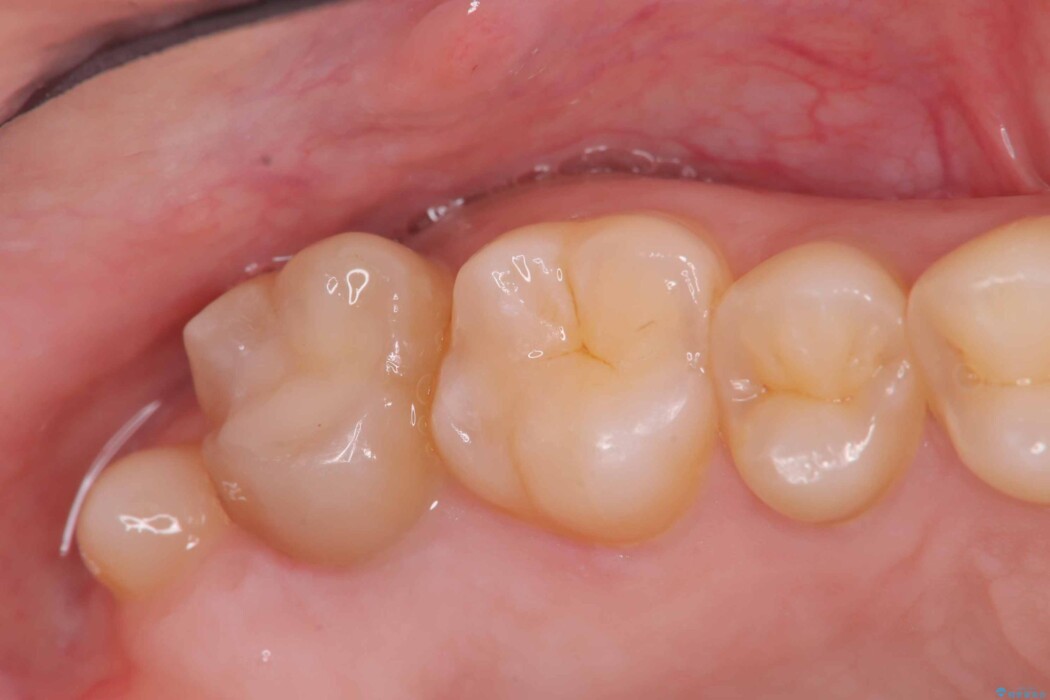

除去後は、再発リスクを抑え長期的な安定を図るために、適合精度が高く劣化しにくいセラミックインレーによる修復を計画しました。